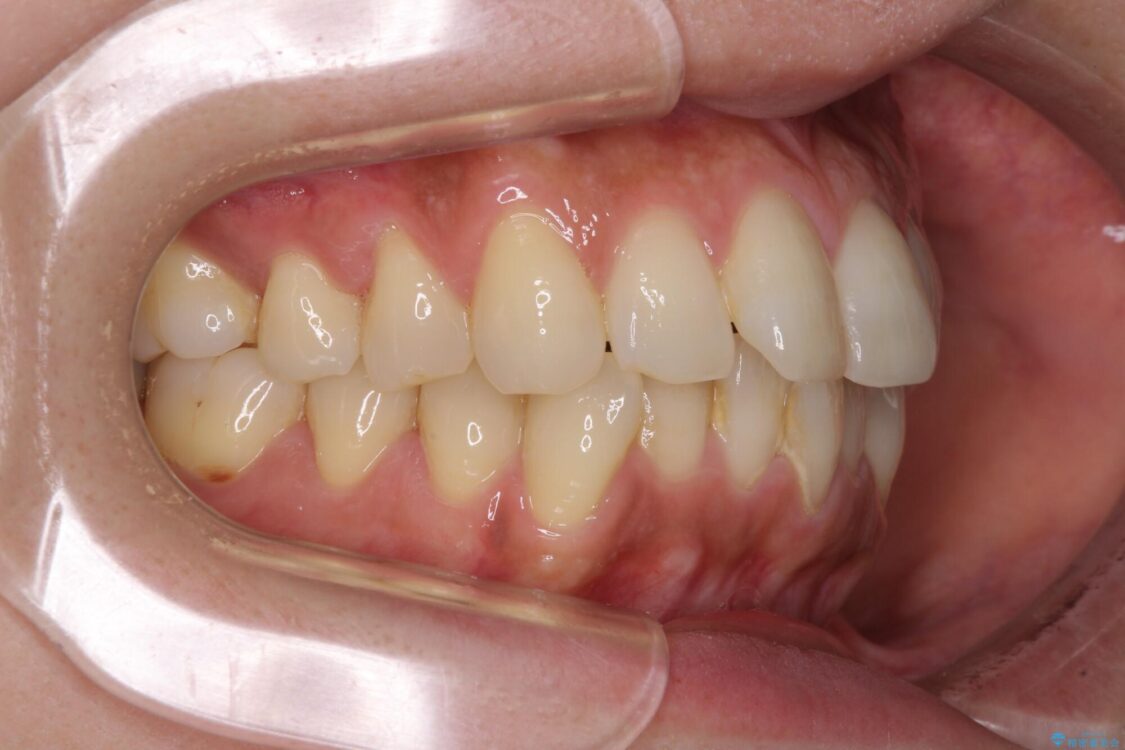

全体的なデコボコと、以前抜歯した歯のスペースを閉じた部分が気になるとのことで来院された患者様です。

左上第一大臼歯を抜歯した際に、スペースを閉じたそうですが、歯が傾斜してものが挟まって不快とのことでした。

治療前

• インビザラインによる矯正治療と奥歯のインプラント治療 治療前画像